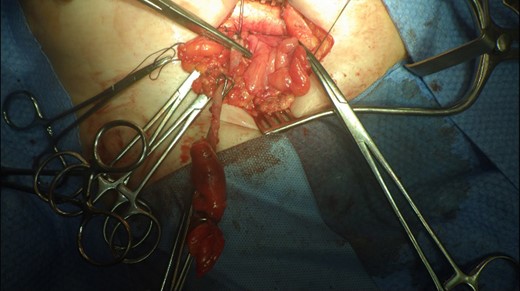

This 82-year-old lady presented with a sudden painful right sided groin swelling not previously noticed. She had no features of obstruction and was opening her bowels and not vomiting. Her medical background included left sided femoral hernia repair in 2005, coronary artery bypass graft and bilateral total knee replacements. On examination her abdomen was soft with the presence of a tender, irreducible swelling in the right groin, inferolateral to the pubic tubercle. She had good bowel sounds and there was stool present in the rectum on PR examination. A full set of blood tests demonstrated no abnormality. A CT abdomen and pelvis demonstrated an incarcerated right sided femoral hernia containing an 8 mm long inflamed appendix with a small amount of localized free fluid and inflammation indicative of De Garengeot’s hernia with underlying acute appendicitis (Fig. 1). The hernia sac diameter measured 2 mm on CT scan. She was taken to theatre for an open Lockwood repair of her femoral hernia and an appendicectomy. Following an initial Lockwood incision over the lump, dissection was performed down to the hernia sac also exposing the inguinal ligament (Fig. 2). The tightness of the femoral ring made mobilization of the appendix difficult. By partially incising the inguinal ligament superior to the femoral ring, the appendix was freed, and on inspection showed inflammation particularly towards the tip (Fig. 3). The caecum was then reduced and the inguinal ligament was repaired with non-absorbable suture. The femoral hernia was then repaired with a small funnel of ultrapro mesh. Appendicectomy was then performed in the usual fashion via the Lockwood incision leaving a slightly longer stump than usual (Fig. 4).

Excised appendix specimen with a slightly longer than usual appendix stump.

The patient had an uneventful recovery and was discharged on the second postoperative day. Subsequent histopathology of the appendix specimen demonstrated serosal inflammation throughout the appendix with partial fibrotic obliteration of the appendix lumen. No formal follow-up was organized and to date there have been no complications following surgery.